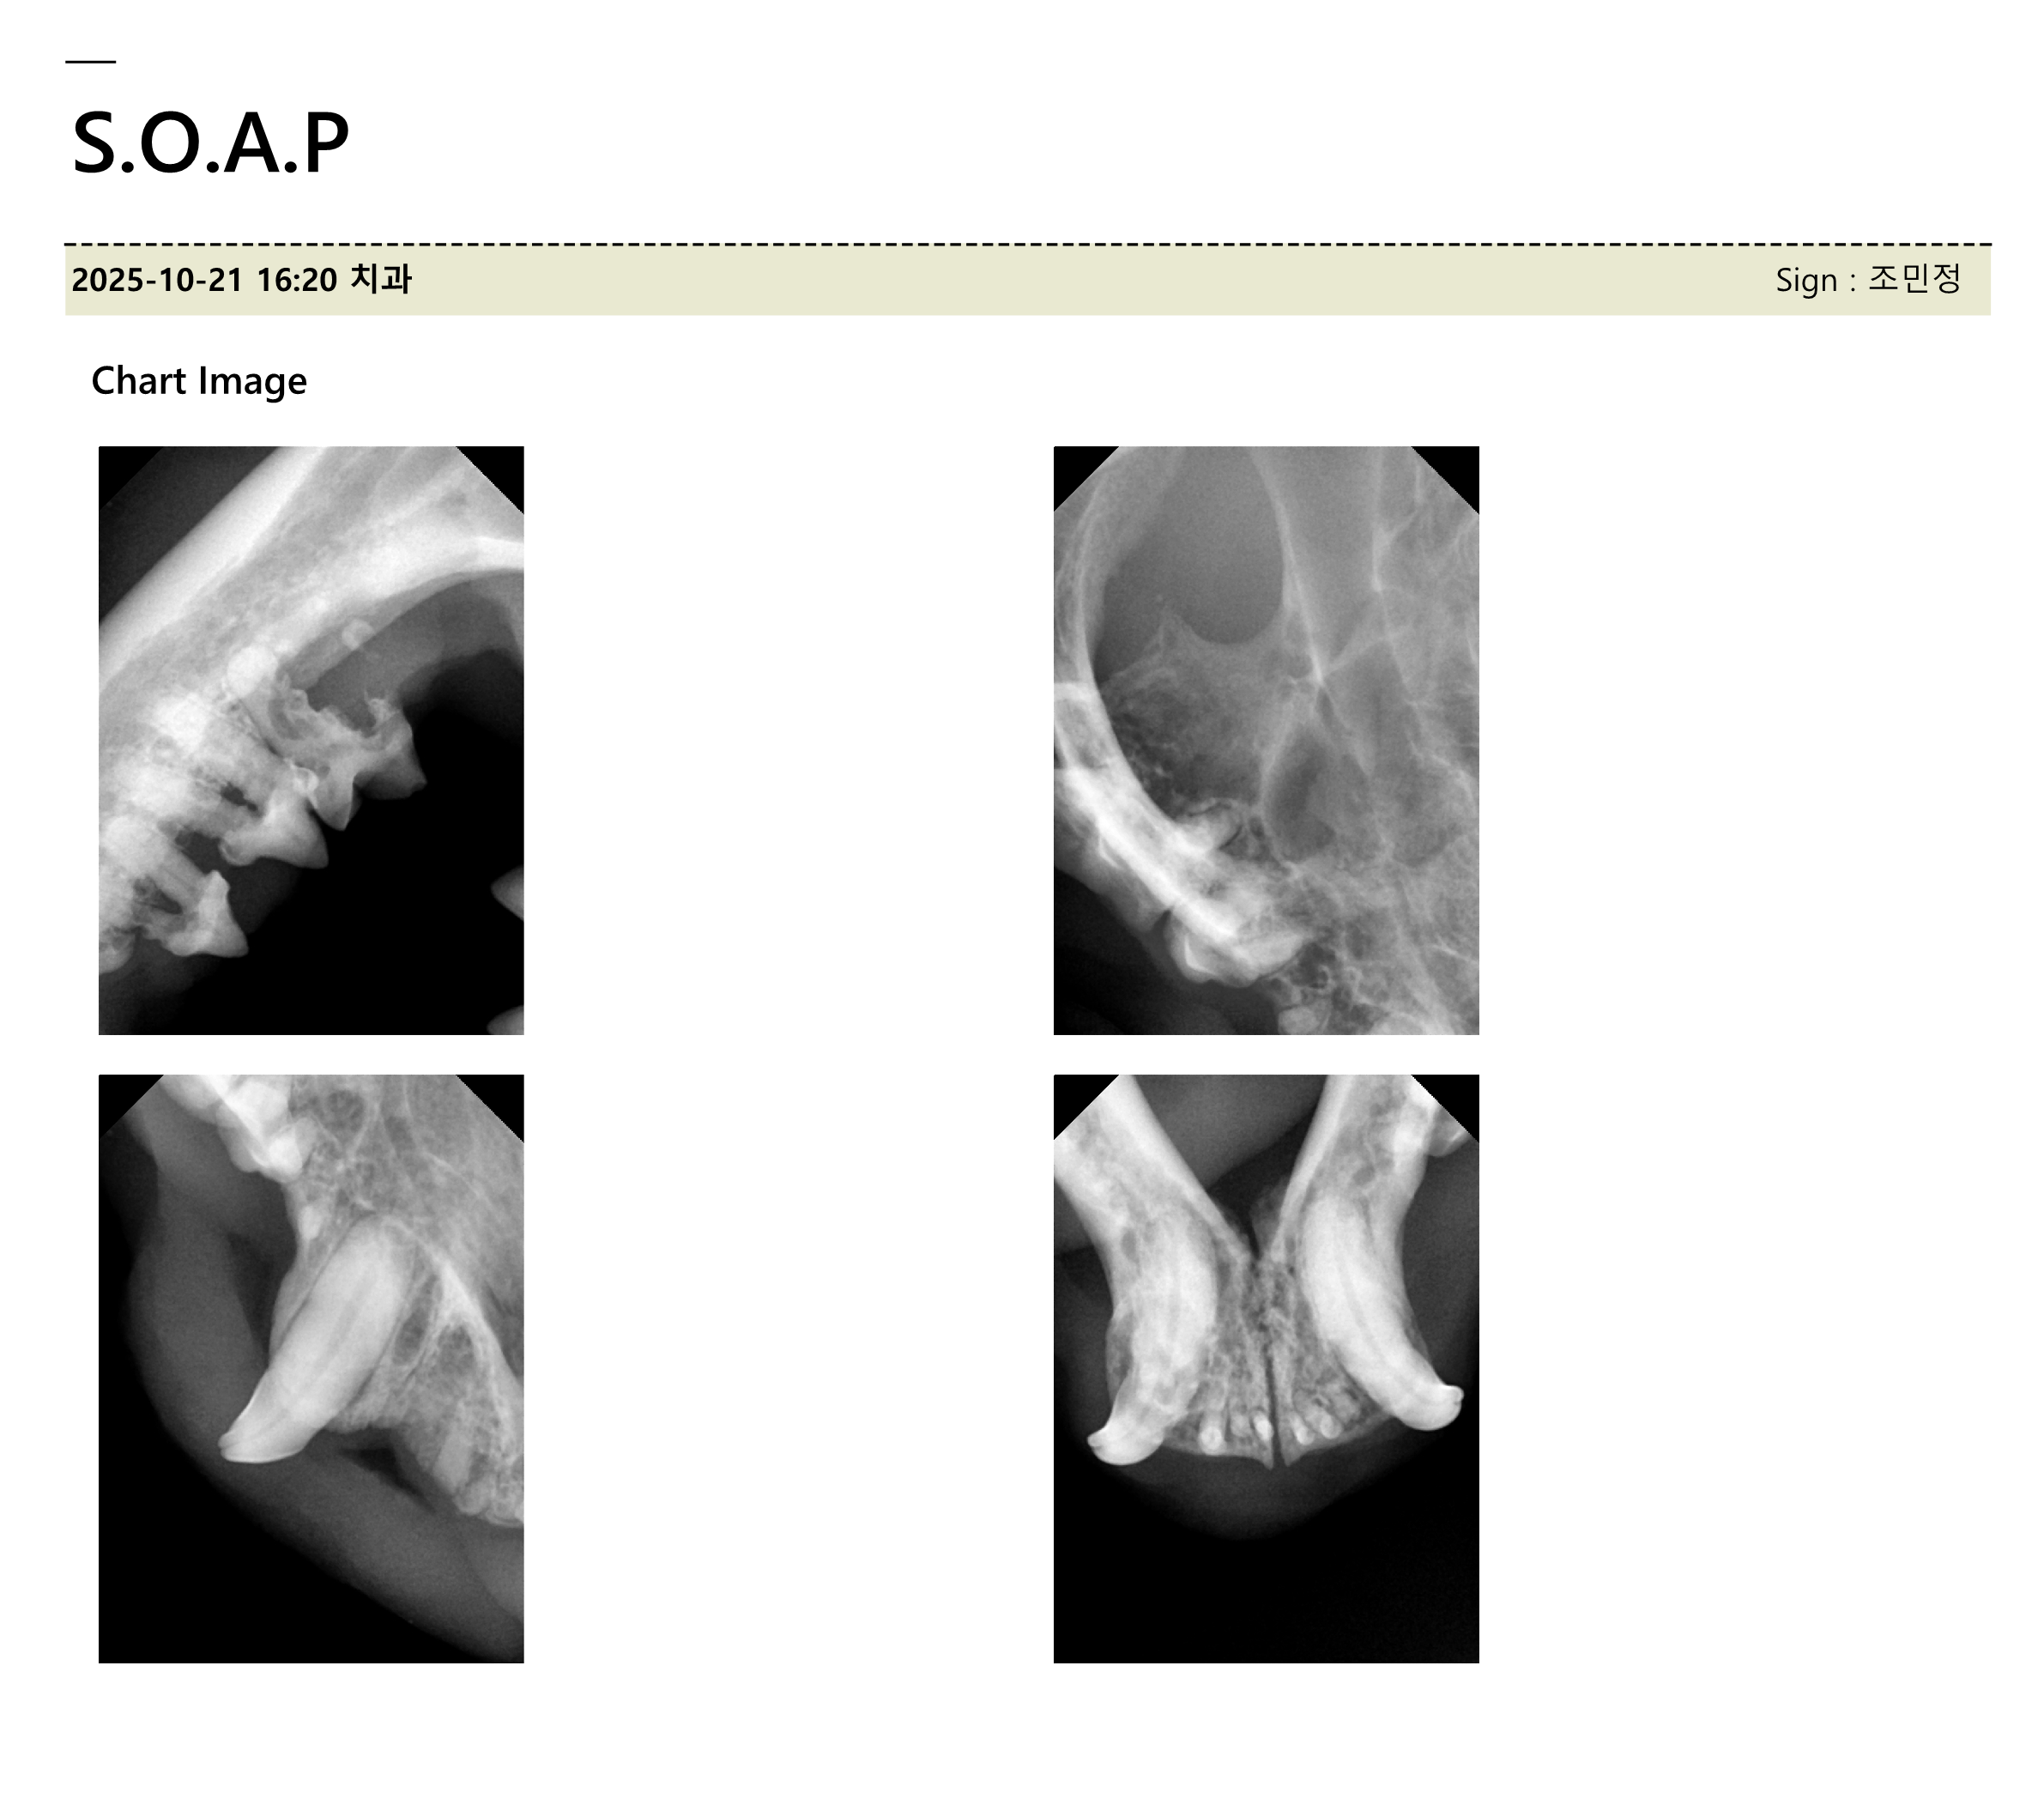

| 치료과정 | 호빵이는 저녁에도 습식을 먹으러 매일 나오지는 않던 녀석이라 구조가 걱정이었습니다. 습식 시간에 나타나길 기다리다가 한 차례 구조에 실패해 마음을 졸이게 했지만, 겨울집이나 여름집을 마련해 두는 곳에는 잘 머무르곤 했기에 이튿날인 10월 21일(화) 낮에 급식소와 집을 마련해 둔 곳 근처에 포획틀을 설치했고 무사히 구조할 수 있었습니다. 미리 연락해 둔 병원으로 곧바로 이동하였고, 사납고 사람 손을 타지 않는 성격인 터라 마취한 후 대기 시간을 가진 후 본격적인 검사에 들어갔습니다. 이 병원에서는 마취 후 상태를 보고 발치가 필요한지 아닌지를 판단한다고 하였는데요, 호빵이는 오랫동안 구내염을 앓아 왔기에 전발치가 필요한 상태임을 진단받았습니다. 그렇게 당일 모든 이빨에 대한 전발치를 진행하였고, 특히 목 안쪽에 염증이 심했던 상태라 조금 편하게 호흡을 할 수 있도록 추가적인 처치를 해 주셨다고 했습니다. 또 2주 동안 효과가 지속되는 항생제 처치도 진행하였습니다. 불행 중 다행히도 혈액 검사 결과 별다른 문제는 더 발견되지 않았습니다. 병원 방침상 발치 후 당일 퇴원한다고 하였으나, 힘든 수술을 한 아이를 바로 방사할 수는 없어 하루 동안 입원을 부탁드렸고 다음 날인 10월 22일(수) 오전에 호빵이를 데려와 원래 지내던 곳에 제자리 방사하였습니다. |

| 대상묘 치료중 사진 | ![]() ![]() ![]() ![]() |

[치료 중 사진]